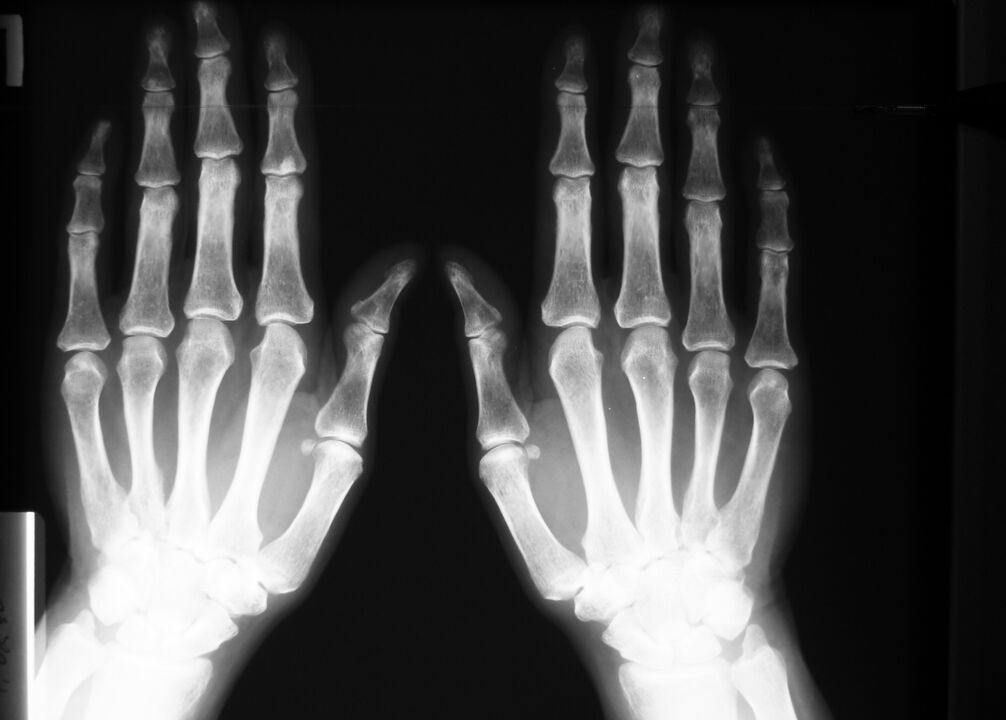

Para doenças degenerativas e lesões – alterações nas articulações: tecido ósseo e cartilaginoso, que podem ser observadas em radiografias ou resultados de tomografia computadorizada.

A ressonância magnética também dará um quadro completo das alterações nos tecidos moles em caso de inflamação do tendão, em caso de ruptura de um ligamento ou músculo.